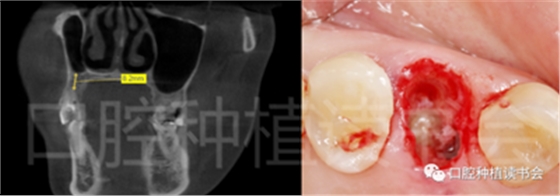

術前CBCT(美亞光電)檢查:47根分叉下方骨高度及骨寬度滿足即刻種植要求(圖13)。

圖13 47根分叉區(qū)骨寬度及骨高度(與下頜神經(jīng)管之間的距離)滿足即刻種植要求。

5.3.6 術后即刻CBCT(美亞光電)檢查種植體軸向及深度良好(圖19)。

圖19 術后即刻CBCT確認種植體頰、

舌側(cè)骨板完整,并保持了足夠的厚度。